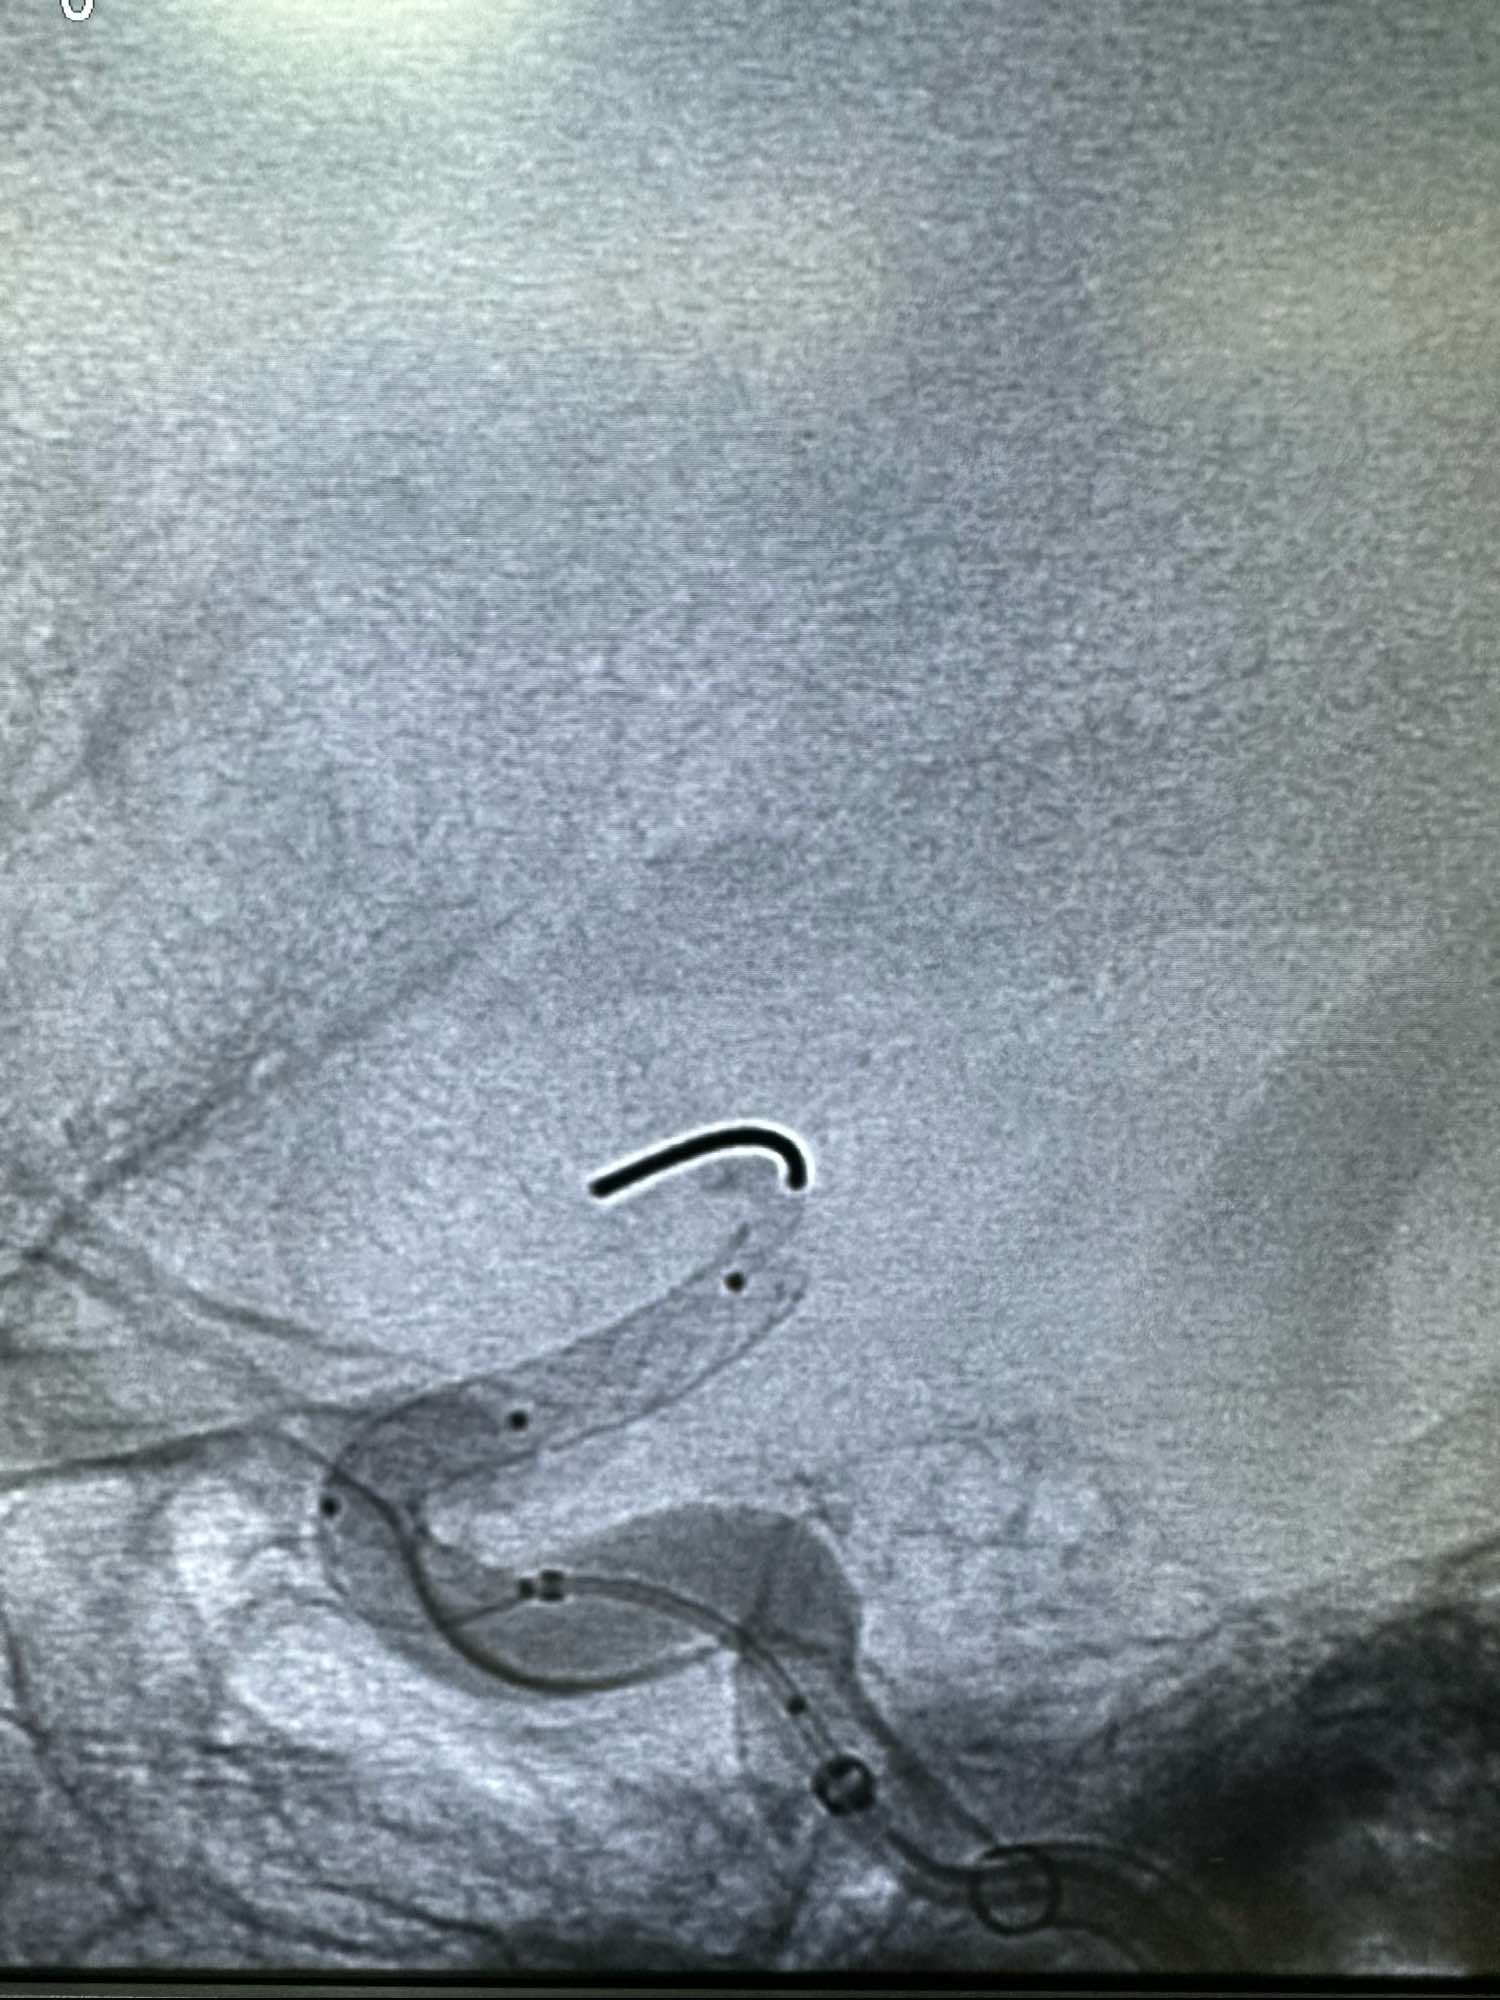

直接Neuromax长鞘加上5F的CAT 5F的115中间导管作为支撑